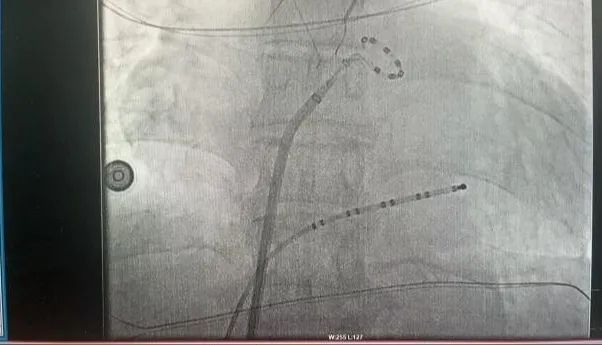

近日,延安大學咸陽醫(yī)院成功實施了咸陽地區(qū)首例脈沖場消融術、首例脈沖場消融+左心耳封堵“一站式”治療房顫手術2例手術的順利完成,標志著我院在心律失常治療技術上的又一重大突破!

此次手術患者均為持續(xù)性房顫患者,由延安大學咸陽醫(yī)院吳棟梁院長、心律失常專家劉雄濤副院長帶領介入團隊開展,安全高效、圓滿完成手術,手術過程患者全程清醒,術中自訴感覺良好,無痛苦感受。術后患者的心律恢復并維持了竇律,目前恢復情況良好,無任何并發(fā)癥出現。